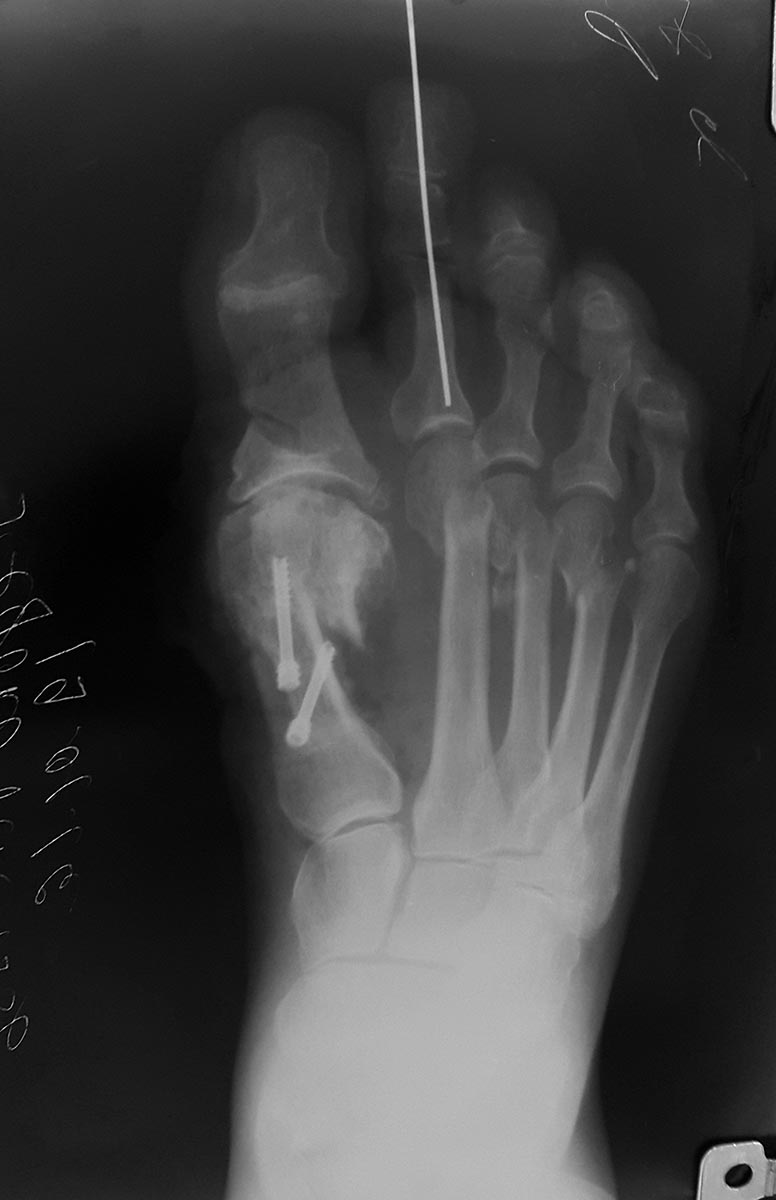

Сделал Обьем такой

scarf, Akin.

открыто вейль 2,3 с удлиннением длинного разгибателя 2 пальца, закрыто

субкапитальная остеотомия 4 пальца.

хохман 2 фиксация спица 3 недели.

Оцените пожалуйста ситуацию. Вторые сутки отека нет все нормально со стопой